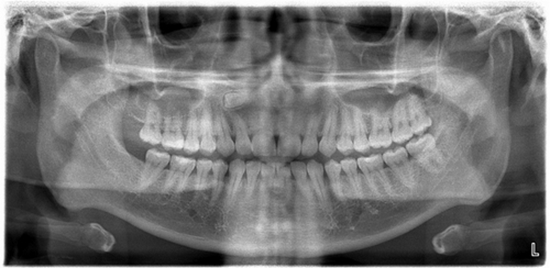

Tonsilolith in Routine Panoramic Radiographies Is It a Common Incidental Finding?

The present study demonstrated that tonsiloliths may be accidentally detected through panoramic radiographs in nearly 5% of cases. There is no gender-based predisposition, and tonsiloliths are more common in the 41 to 60-year-old group.

Panoramic Radiographies {faces}

Tonsiloliths should be the first differential diagnosis when multiple opaque lesions with ill-defined borders superimposed on the palatal uvula and the ramus are detected on a panoramic radiography in a middle-aged patient. A correct diagnosis will eliminate the need for further evaluations including radiography and clinical examinations.